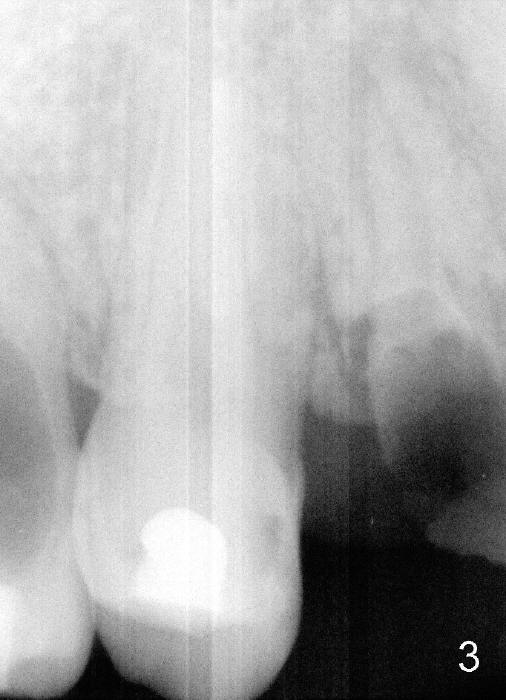

A 25-year-old black man has poor dentition. The tooth #5 is non-salvageable (Fig.1-6). Although the 1st bicuspids belong to the posterior teeth, anterior sensor holders should be used to show the sinus floor (Fig.1,2: ^). In contrast, PAs in Fig.3,6 (trimmed mesiodistally) are taken with posterior sensor holders; the sinus floor is out of view.

A long implant will be placed (possible 4.5x20 mm, Fig.2). A typical 1st bicuspid has 2 canals. In this case, there are most likely two roots (Fig.3): buccal (Fig.4 green dashed line) and lingual (Fig.5 pink dashed line).

It is reasonable to assume that the roots of the tooth #5 are bifurcated. If it is confirmed after extraction, a D implant may be more appropriate for this case (1, 2, 3).